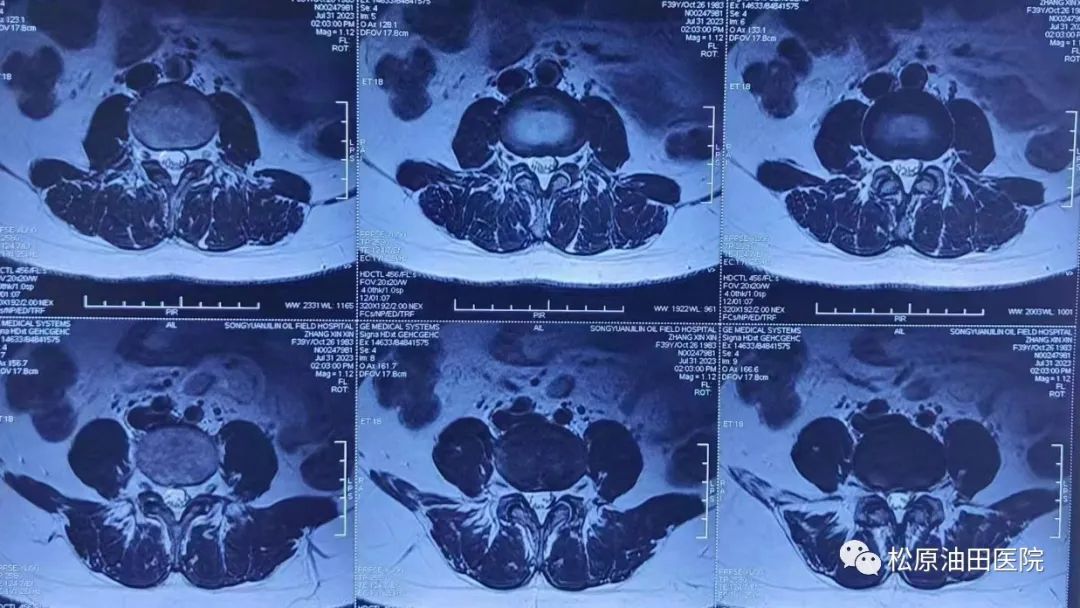

该患者为一名年轻女性患者,她腰疼伴左下肢麻木疼痛七个月,加重两个月,患者非常痛苦,已严重影响了她的工作和生活。患者也曾走了多家医院咨询治疗未果,最终选择油田医院骨二科进行手术。通过术前的辅助检查及临床的查体,骨二科最终决定采用后路椎间孔镜下腰椎间盘摘除手术治疗。

据了解,腰椎间盘突出症是临床上最为常见的腰部疾病,患者因为腰部间盘退变突出之后压迫神经根,常出现腰疼、下肢麻木疼痛及伴有明显的活动受限,严重的患者连下床都受影响,严重影响日常生活。传统的腰椎手术为开放式手术,间盘摘除彻底,但创伤很大,患者术后恢复需要较长时间,而且年轻患者一旦腰椎开放手术之后,临近节段退变加速,让很多患者难以接受,致使很多腰椎间盘突出症患者得不到有效的诊治。随着科学的进步,技术的发展,很多腰部的疾病都可以通过微创的方式进行完成,脊柱内镜下治疗腰椎间盘突出症已经成为了现在的主流治疗方式。

据骨二科医生范立军介绍说,脊柱内镜技术创伤非常小,创口基本不出血,不需要放置引流,术后不需要特殊处置。但是由于所有的操作都是在镜下的狭小空间完成,需要很强的空间立体感及对局部解剖的熟悉,同时还需要双手协调镜子及操作器械,以防镜子对脊髓的直接损伤,因此后路脊柱内镜间盘手术技术难度高,风险大,有脊髓损伤及下肢瘫痪等诸多手术风险,因此需要术前的精细准备,术中的细致操作,及其较高的技术水平要求及经验。